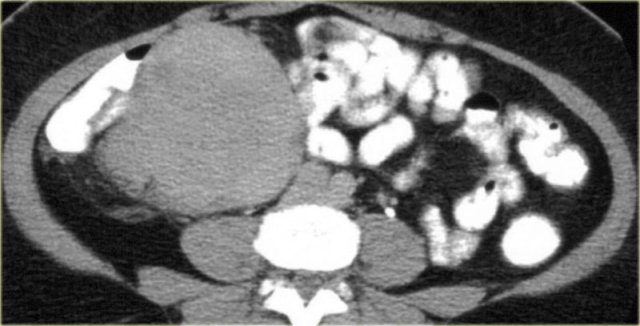

Peritoneal inclusion cyst (4)

On the left images of a male patient, who presented with a lower abdominal mass.

There is a multi-cystic mass extending from the pelvis along the right paracolic gutter to the upper abdomen.

In a male patient this is a very uncommon diagnosis.

These images look quite similar to images of a pseudomyxoma peritonei which was discussed before.

In peritoneal inclusion cysts however, you will not see scalloping of the surface of the liver.